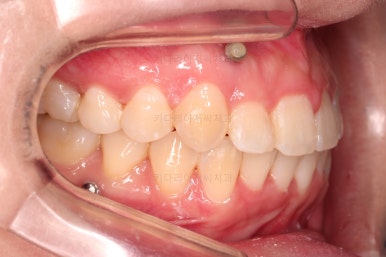

부산비대칭교정 마무리 때의 입안의 모습입니다.

가지런한 느낌은 좋지만 정중선 당연히 약간 안맞고요.

폭도 100%는 안맞아서 어금니쪽이 약간 애매한 교합이기도 했습니다.

하지만 이정도의 비대칭 상황에서 이정도의 교합은 교정만으로 할 수 있는 베스트가 아닌가 생각됩니다.

전후 비교 사진인데요.

입매가 비발치임에도 불구하고 매우 좋아졌고요.

치열과 교합도 매우 좋아졌습니다.

웃을 때 보이는 치열의 기울기도 좋아졌고요.

입을 다물었을 때 입술의 기울기도 처음보다는 좋아졌는데 앞서 말씀드린대로 뼈의 위치가 좋아졌다거나 뼈의 형태가 개선되어서 그런게 아니고요. 치열이 가지런해지고 입이 들어감으로서 입술이 다물어지는 편안한 정도가 바뀌면서 마치 입술의 비대칭까지 좋아진 듯한 착시효과가 생기는 것입니다.

비대칭은 여전히 비대칭입니다.

다만, 그 안에서 최대한 양호한 교합과 모양을 찾아가는 것이 이번 부산비대칭교정 치료의 목표였고, 그런 목표에서는 상당히 만족스럽게 치료가 끝났다고 판단됩니다.